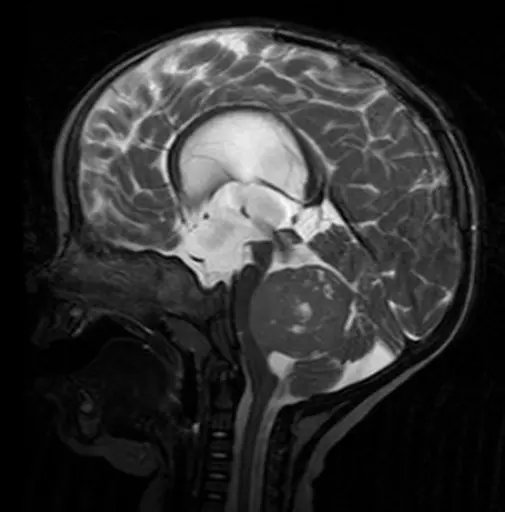

MRT-Aufnahme eines Medulloblastoms